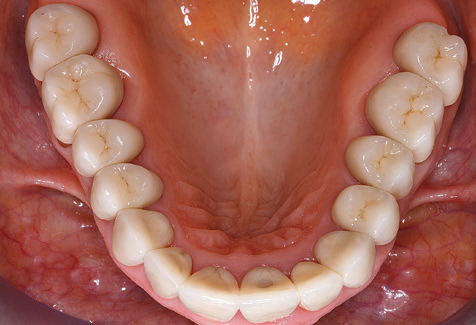

Due to the presence of periodontal disease, SPT was performed every three months in the first years following the insertion. The patient demonstrated a high degree of motivation and good compliance. The pocket depths recorded annually revealed a stable periodontal situation with a BOP index of below five per cent. On the basis of the stable periodontal situation and good cooperation on the patient’s part, the recall interval was extended to every six months as of the sixth year of the prosthetic function phase. Following the change in the recall interval, the respective annual documentation of the periodontal status continued to reveal a stable periodontal situation with no increase in the pocket depths and a BOP index below five per cent (Fig. 2a and b).

The ten-year check-up revealed no indications of advancing clinical attachment loss or peri-implant bone substance loss (Fig. 3).

The patient continues to visit the clinic every six months for SIT. In the following, the patient is taken as an example for demonstrating the individual working steps in a structured SPT session as it has been performed with barely any modifications over the last 12 years. Of course, some new materials and devices have been integrated into the concept over the years. This clinical case report presents the current material and device concept.

Standardised and regular risk-adapted care in the scope of SPT is the key to treatment success for the clinical long-term success in periodontically compromised patients. This is particularly true for patients fitted with implants following successfully completed periodontal treatment (Fig. 11a and b).